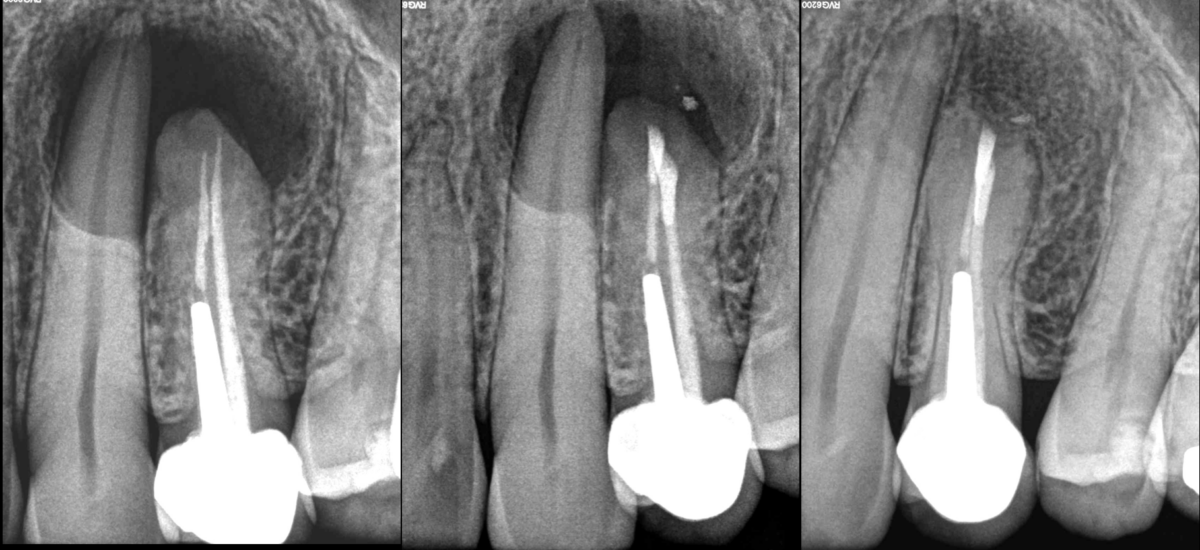

⚠️ Toujours prévenir le patient qu’une nécrose pulpaire de la 23 est possible suite à la chirurgie endodontique de la 24.

💡 Le cas échéant, un traitement canalaire sera indiqué.

📆 À 1 an, la 23 est bien vivante et ne nécessite aucune thérapeutique endodontique.